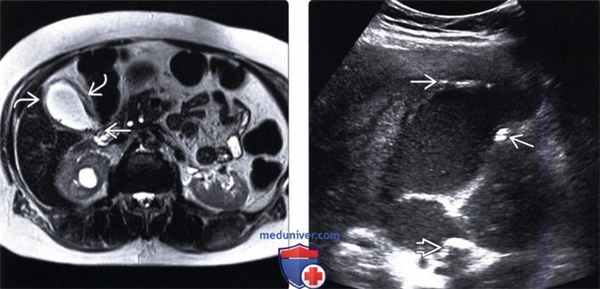

(Левый) МРТ в режиме Т2 HASTE. На аксиальном срезе у пациента с острым кальку-лезным холециститом визуализируются множественные мелкие конкременты и интрамуральный отек.

(Правый) На продольном косом УЗ срезе у пациента с острым эмфизематозным холециститом видны растянутый заполненный сладжем желчный пузырь и вколоченный конкремент. Источником ярких интрамуральных эхосигналов является газ.